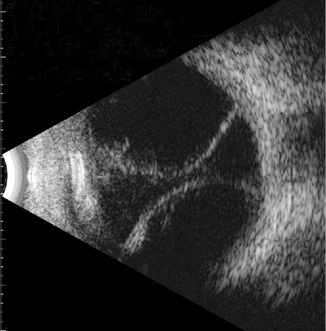

Choroidals can be visualized clinically on fundus examination, where they appear as up to four smooth and dome-shaped (convex) lobes of choroidal elevation with fluid accumulation. Ultrasonography can also be useful, especially in eyes with miotic pupils or other media opacities. B-scan ultrasonography can help to distinguish serous from hemorrhagic choroidals.2 With serous choroidals, B-scan ultrasonography shows dome-shaped retinal elevation with echolucent (dark) subretinal fluid (Figure 1). The retina does not move on dynamic ultrasonography, unlike with a retinal detachment. In severe cases, central retinal apposition—or kissing choroidals—can be seen (Figure 2).

Figure 2. Near-kissing serous choroidals in a patient who developed hypotony after glaucoma drainage device surgery.